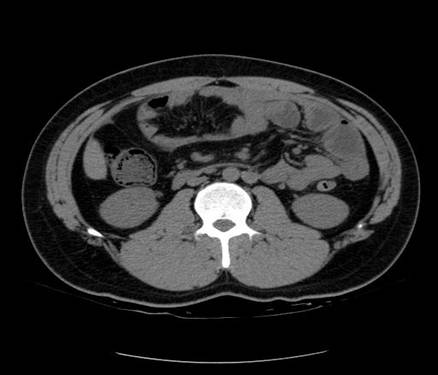

以下是引用zsl6918在2007-6-22 21:08:00的发言:[br]病史较长,反复发作,基本排除恶性病变,腹部定位像可见是小肠梗阻征象,原因无非是肠源性,血管性和神经性的,肠源性的在排除占位后应想到 肠旋转不良的可能,血管性的应想到肠系膜血管的栓塞,神经性的要想到植物神经功能紊乱的可能,本病例应该强化检查帮助诊断,个人感觉旋转不良可能性大。

以下是引用青莲居士在2007-6-24 12:27:00的发言:[br]肠梗阻[br]肝内胆管结石